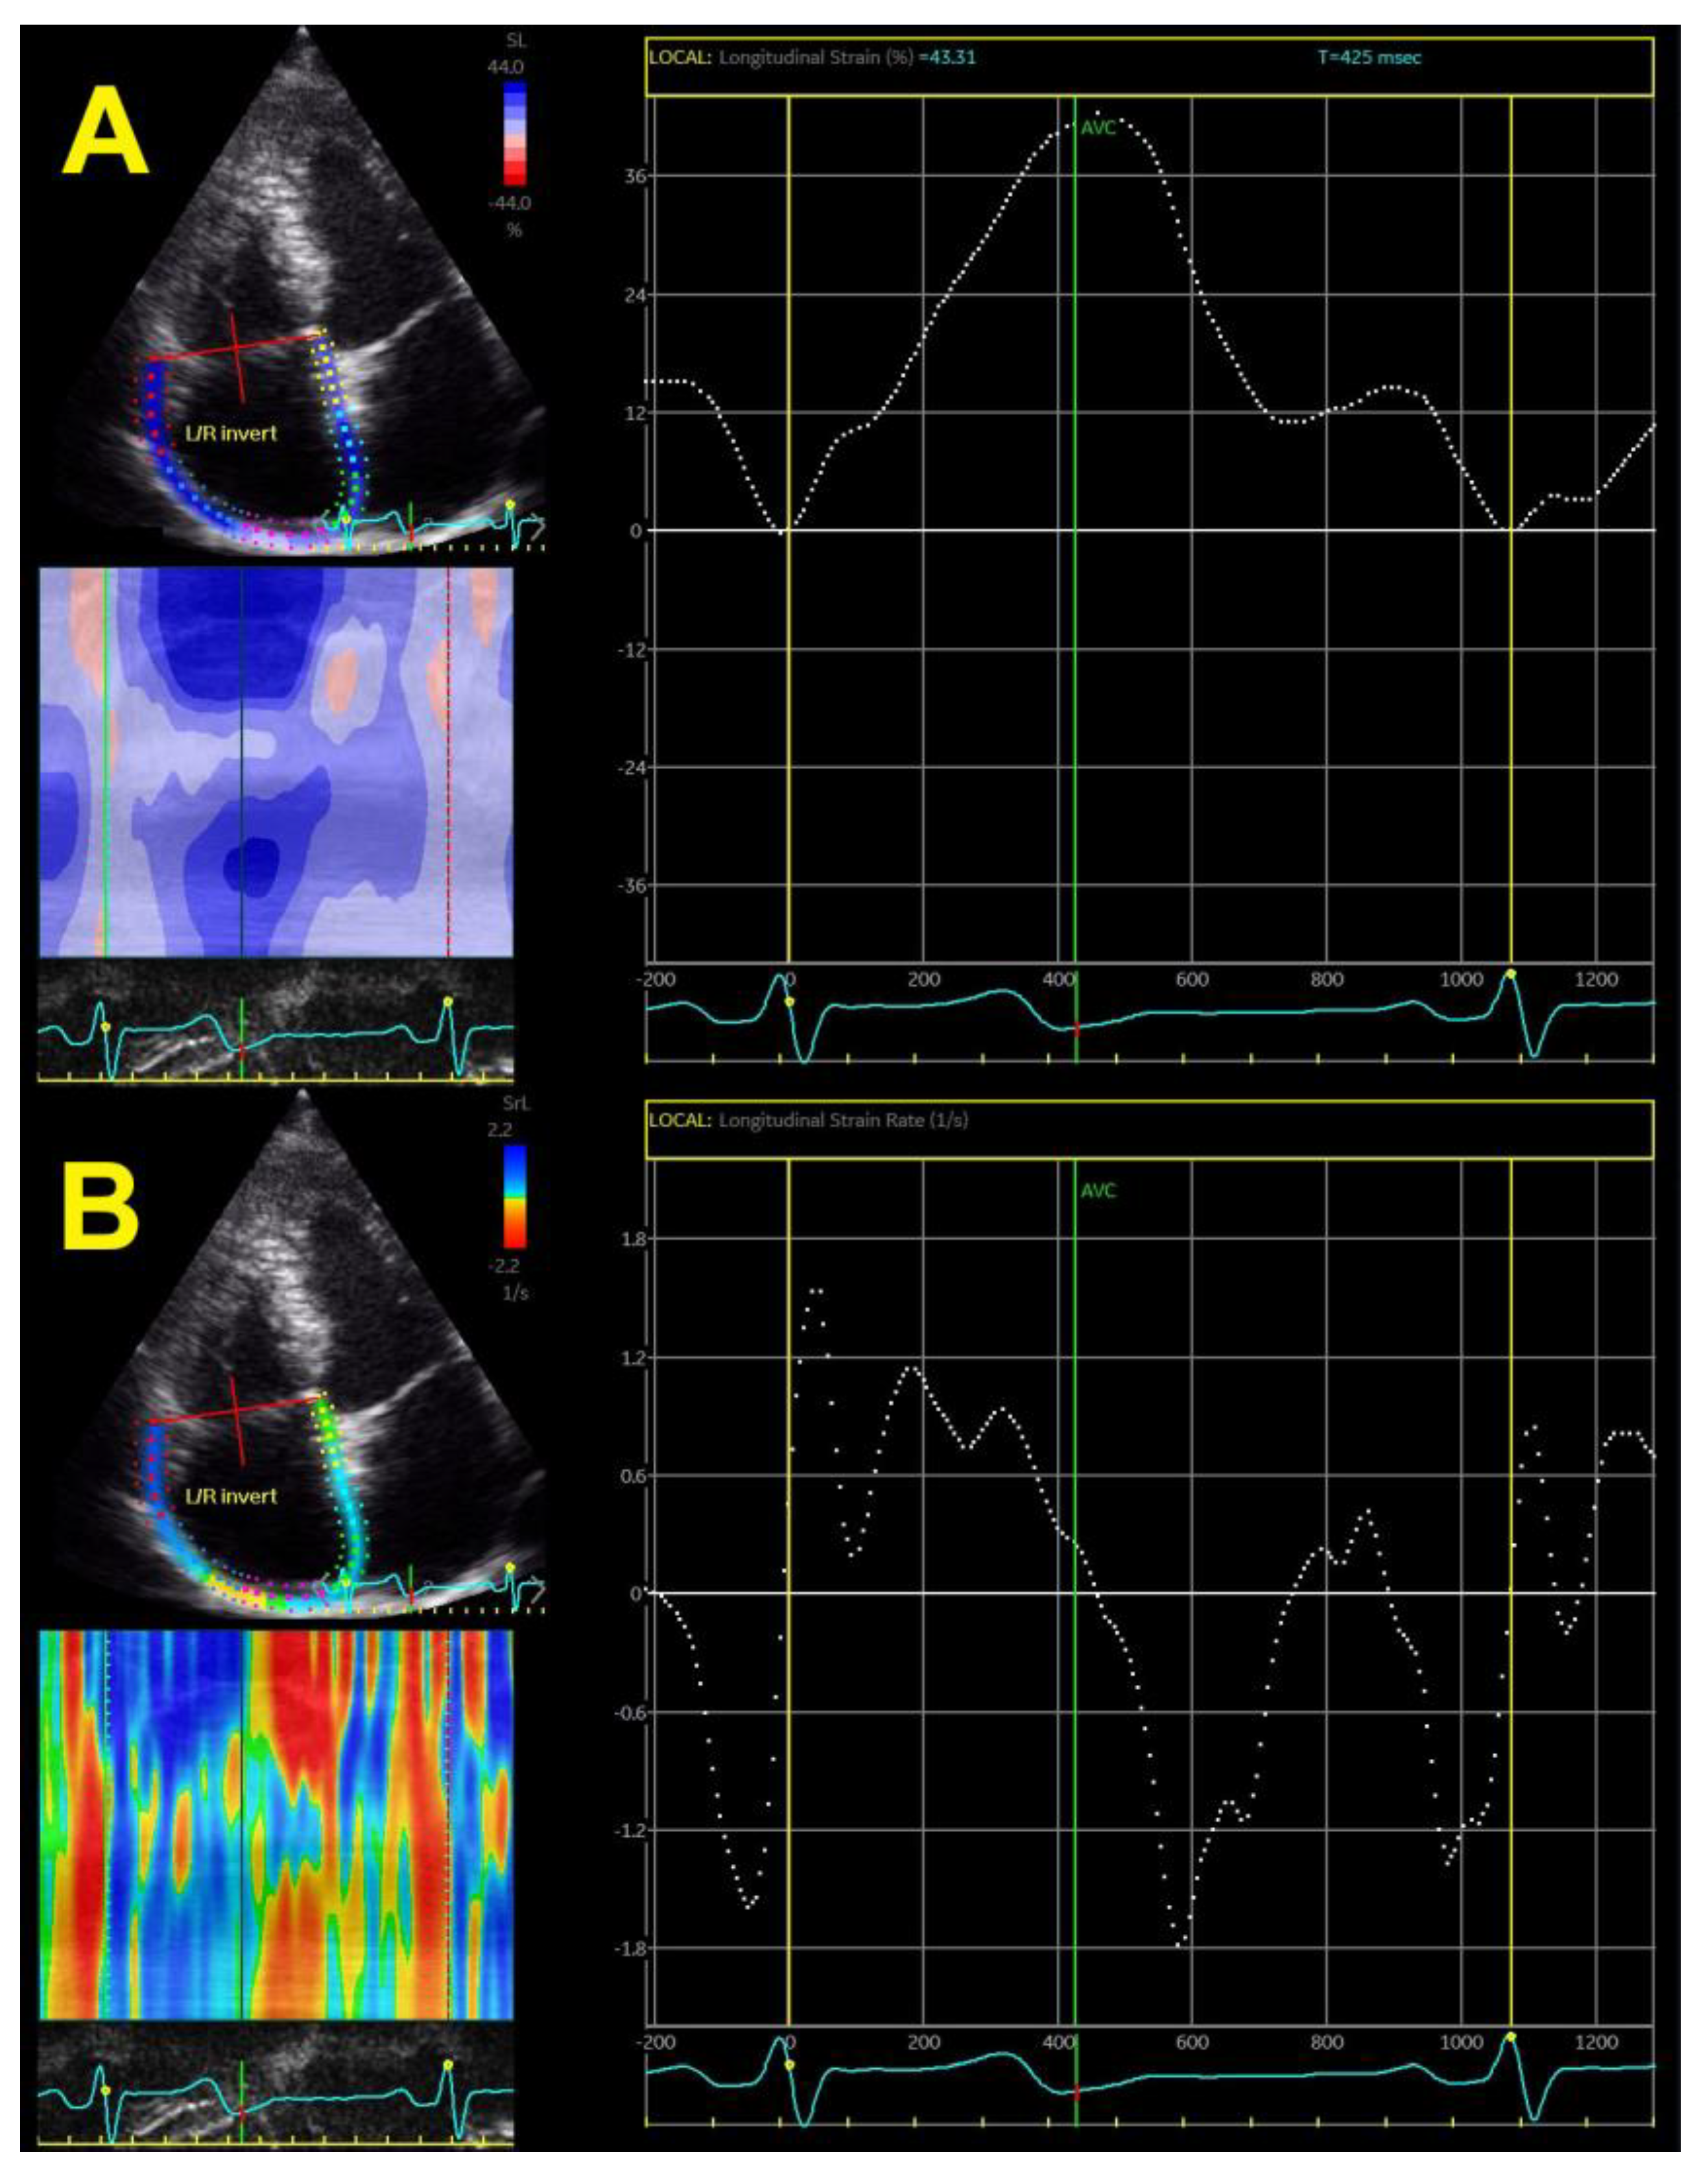

The speckle tracking-derived RV longitudinal strain has been the only method used in the last decade (Figure 3A), whereas the tissue-Doppler-derived strain has not been used for evaluation for a long time due to many limitations. This technique also provides a calculation of strain rates (systolic, early, and late diastolic strain rates) (Figure 3B), which is the speckle tracking equivalent to parameters obtained by tissue Doppler, giving data on systole and early and late diastole. Novel echocardiographic methods enable the assessment of epicardial and endocardial RV longitudinal strain rates (Figure 3C), which has also been used in the hypertensive population.

Figure 3.

Two-dimensional global right ventricular strain (A), right ventricular strain rate (B), and layer-specific strain—endocardial, mid-myocardial, and epicardial (C).